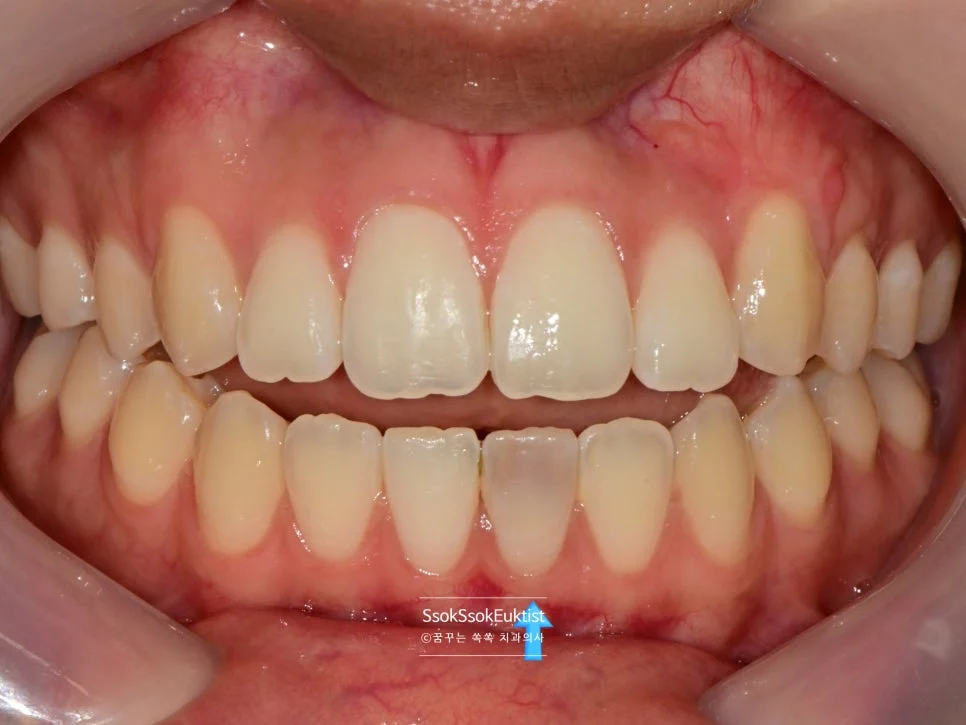

최종 결과 — 레진 충전까지 완료, 어느 치아를 치료했는지 모를 정도로 자연스러운 모습

어떤가요?^^ 어느 치아를 치료했는지도 모를 정도로 원래의 색으로 돌아왔습니다. 박수 박수!!